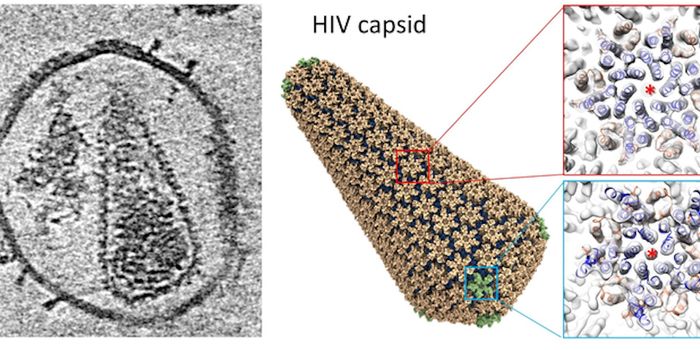

APR 04, 2022Cell & Molecular BiologyAbout 1.5 million new HIV infections are thought to have occurred last year, and while COVID-19 has dominated concerns a ...

FEB 21, 2022Cell & Molecular BiologyTwo people have been cured of HIV, and now, a US woman joins them. In this third case, stem cell transplants were being ...

NOV 30, 2021ImmunologyHIV is a master of disguise. Once the virus enters the body, it has a number of sophisticated mechanisms through which i ...

NOV 22, 2021MicrobiologyThough treatments are available, there is no cure or vaccine from HIV, which impacts about 38 million people worldwide. ...

SEP 06, 2021MicrobiologyHIV vaccines have remained elusive in part because the virus has a powerful ability to mutate, and there are so many str ...

JUN 24, 2021ImmunologyA new study has revealed how stem cells can be used to amplify immune responses to HIV, the virus that causes AIDS. The ...